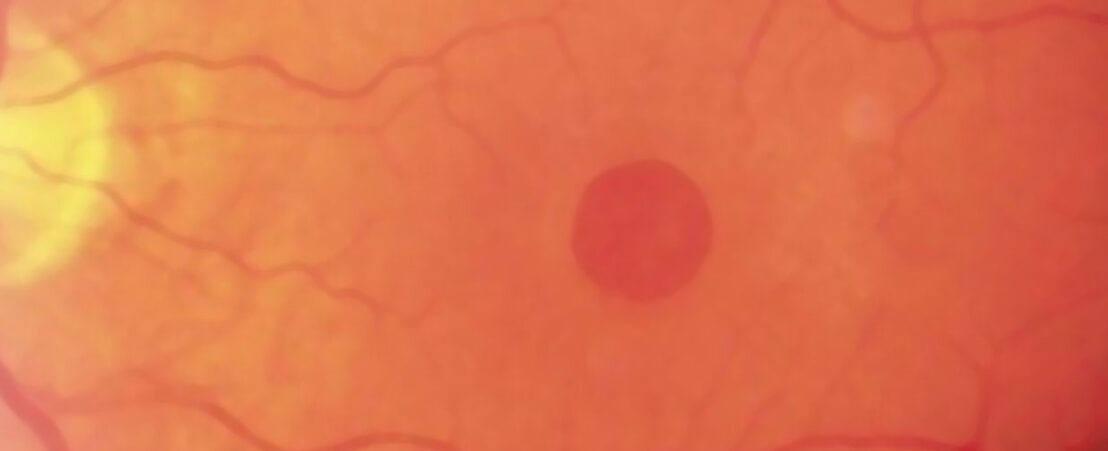

Au stade initial de la maladie, une lésion jaunâtre est détectée dans la fovéa, la partie de la rétine se trouvant au centre de la macula qui est responsable de la vision détaillée et nécessaire pour la lecture. Quand le trou s’est consolidé, il peut être visualisé dans la fovéa.

Degré 1: On détecte un décollement de la zone fovéal de la rétine mais sans trou rétinien complet.

Degré 2: On détecte un trou rétinien complet petit dans la zone fovéale.

Degré 3: Augmentation du la dimension du trou (à partir de 400 micron)

Degré 4: Le trou est associé à un décollement postérieur du corps vitré. Le corps vitré est la gélatine que se trouve à l’intérieur de l’œil.